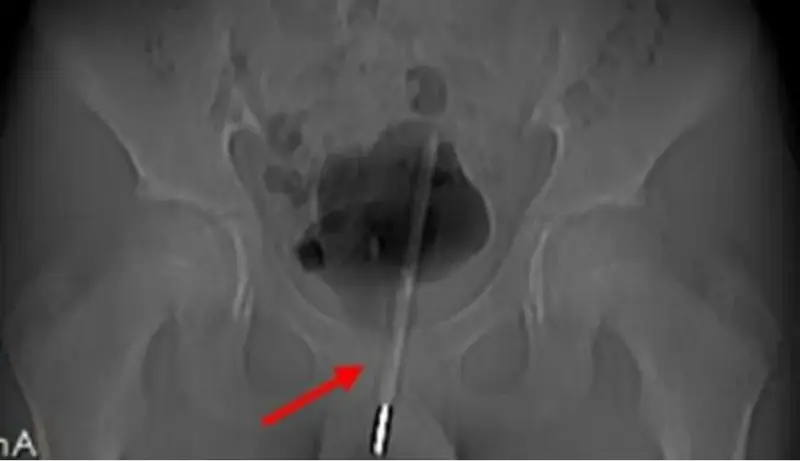

Los rayos x mostraron que se había introducido tanto el termómetro que le llegó hasta la vejiga

Sin embargo, el joven acabó sufriendo un intenso dolor durante nueve horas hasta que fue intervenido de urgencia ya que al parecer y según revelaron los rayos X, el termómetro había sido introducido muy adentro del tracto urinario, tanto que había llegado hasta la vejiga del niño.